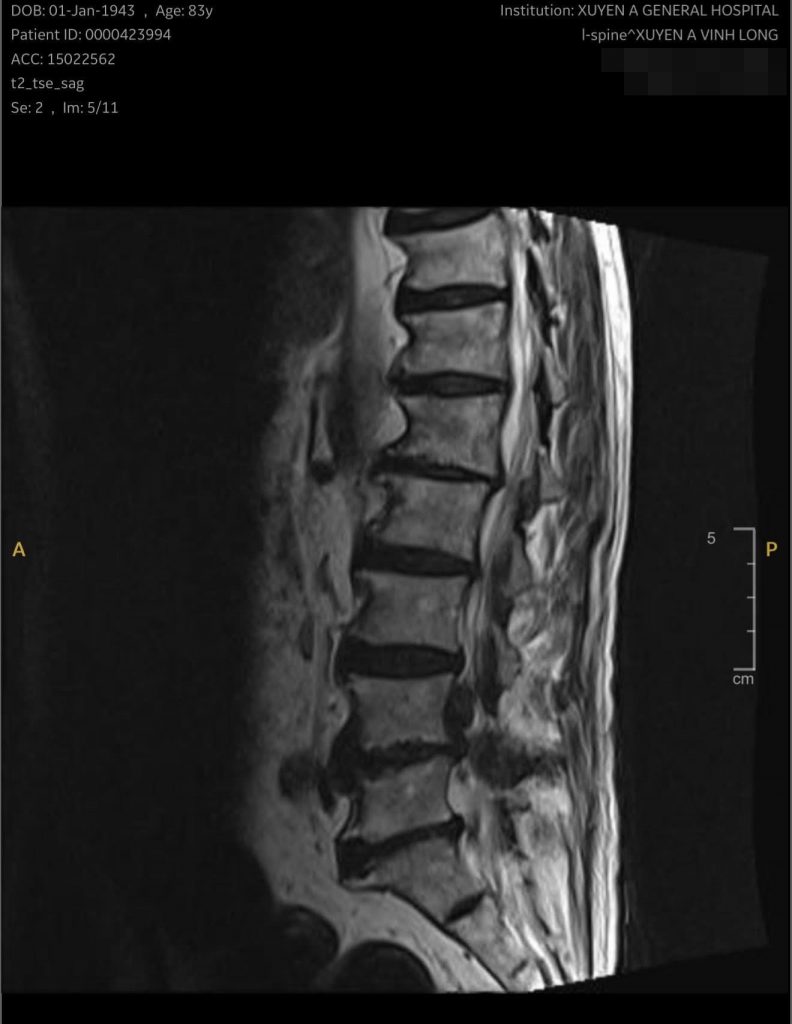

Kết quả chụp MRI cho thấy bệnh nhân bị thoát vị đĩa đệm L4–L5 có mảnh rời chèn ép rễ thần kinh nặng. Nếu chậm trễ điều trị, nguy cơ yếu liệt chân là rất cao. Sau khi được thăm khám, đánh giá toàn diện tình trạng sức khỏe và tư vấn kỹ lưỡng, các bác sĩ Khoa Ngoại Thần kinh đã quyết định phẫu thuật để giải phóng chèn ép và làm vững cột sống cho bệnh nhân.

Hình ảnh cận lân sàng của bệnh nhân phải phẫu thuật cột sống